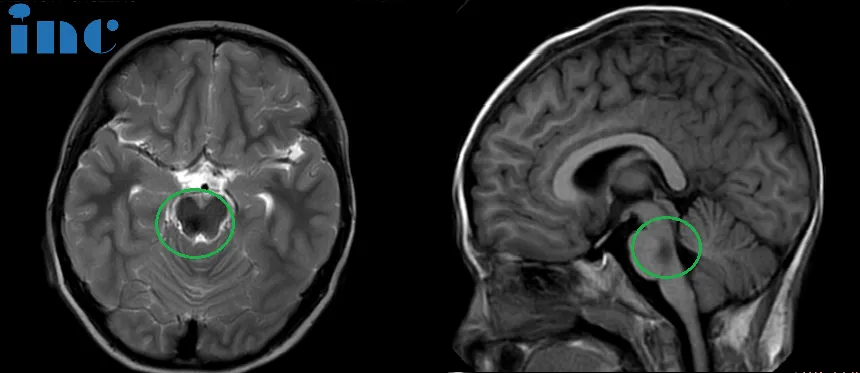

在苏州大学附属儿童医院,不到2岁的聪聪即将迎来人生第一次开颅手术。全家人焦急地等待着手术结果,作为主刀医生的巴特朗菲教授必须全切脑干海绵状血管瘤,才能为聪聪争取到最好的预后——但这绝非易事。“从核磁上可见脑桥血肿,大约16 x 22 x 21mm,第四脑室受压变窄。同时,由于脑干出血,患儿已经出现了双眼斜视、面瘫、不自主扭头、走路不稳等症状,但家属可以放心,我有信心安全全切。”

就在这件事逐渐被淡忘时,在一次聊天中,聪聪父亲向医生友人偶然提起,于是,朋友建议他带孩子做一个脑部筛查,真相就此揭开。“我们在医院做了一个核磁共振,拍出来果然是脑部的问题。当时我都惊呆了,我以为是胶质瘤,结果医生告诉我是脑干海绵状血管瘤。”